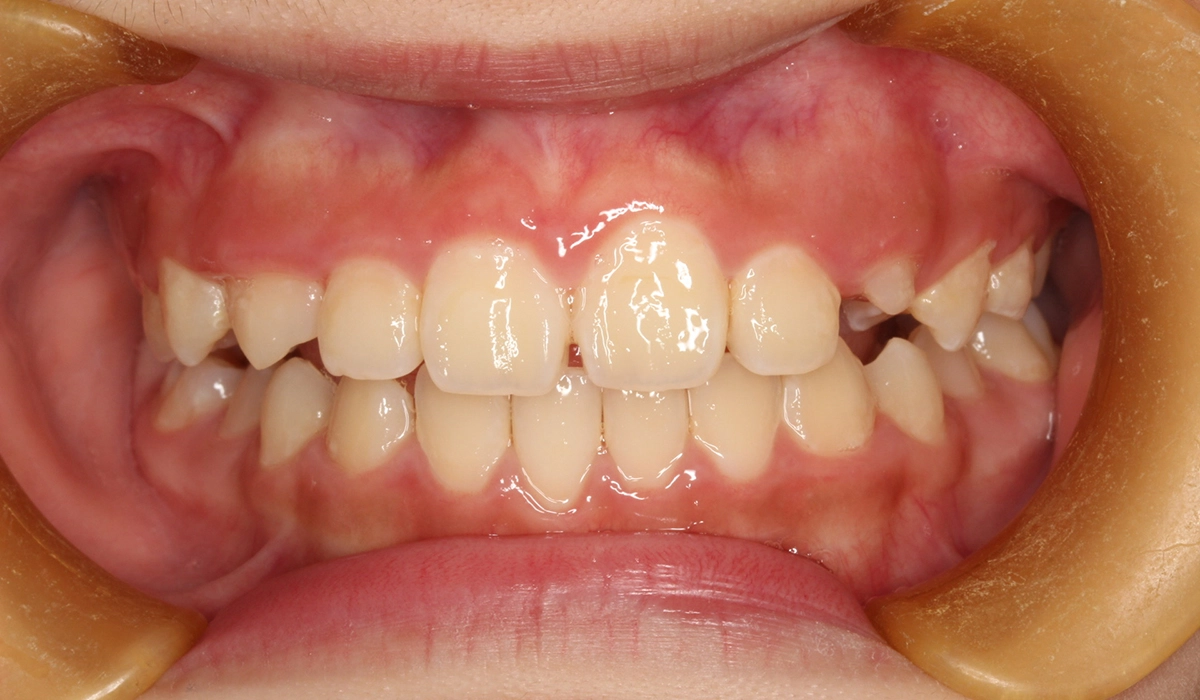

術前:正面

主訴 前歯の捻れが気になる

治療内容 前歯の捻れを気にされており、矯正検査後叢生Ⅰ級と診断いたしました。